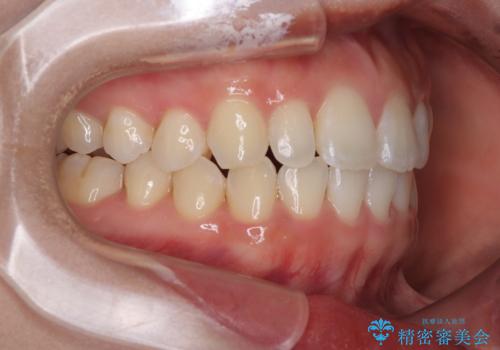

治療終了時

前歯が自然なアーチにきれいに並び、正中(上下の中心線)も整い、咬み合わせも良好です。

側方拡大することで、非抜歯であるにも関わらず前歯が前方に出ることなく、バランスの良い仕上がりとなりました。